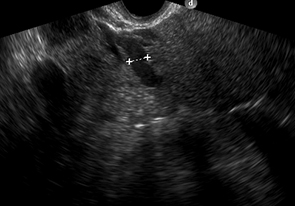

Fig. 2: a) Examen ecográfico por vía transvaginal, que muestra vena ovárica izquierda ectásica de 7.5 mm. b) Examen ecográfico por vía transvaginal, demostrando vena ovárica derecha normal, de 2.5 mm.

Hallazgos imagenológicos. En el eco Doppler ginecológico por vía transvaginal se observa varicocele pelviano (Fig. 1). La vena ovárica derecha mide 3.8 mm, y la izquierda, ectásica, 7.4 mm (Fig. 2). En el eco Doppler abdominal se visualiza la vena renal izquierda, de 3.1 mm en topografía del compás aorto-mesentérico y 8.1 mm en el segmento proximal al riñón izquierdo, con una velocidad 50cm/s en el compas y 30cm/s en el segmento proximal al riñón. El estudio corresponde en primera instancia a un síndrome de Nutcracker (Fig. 3).